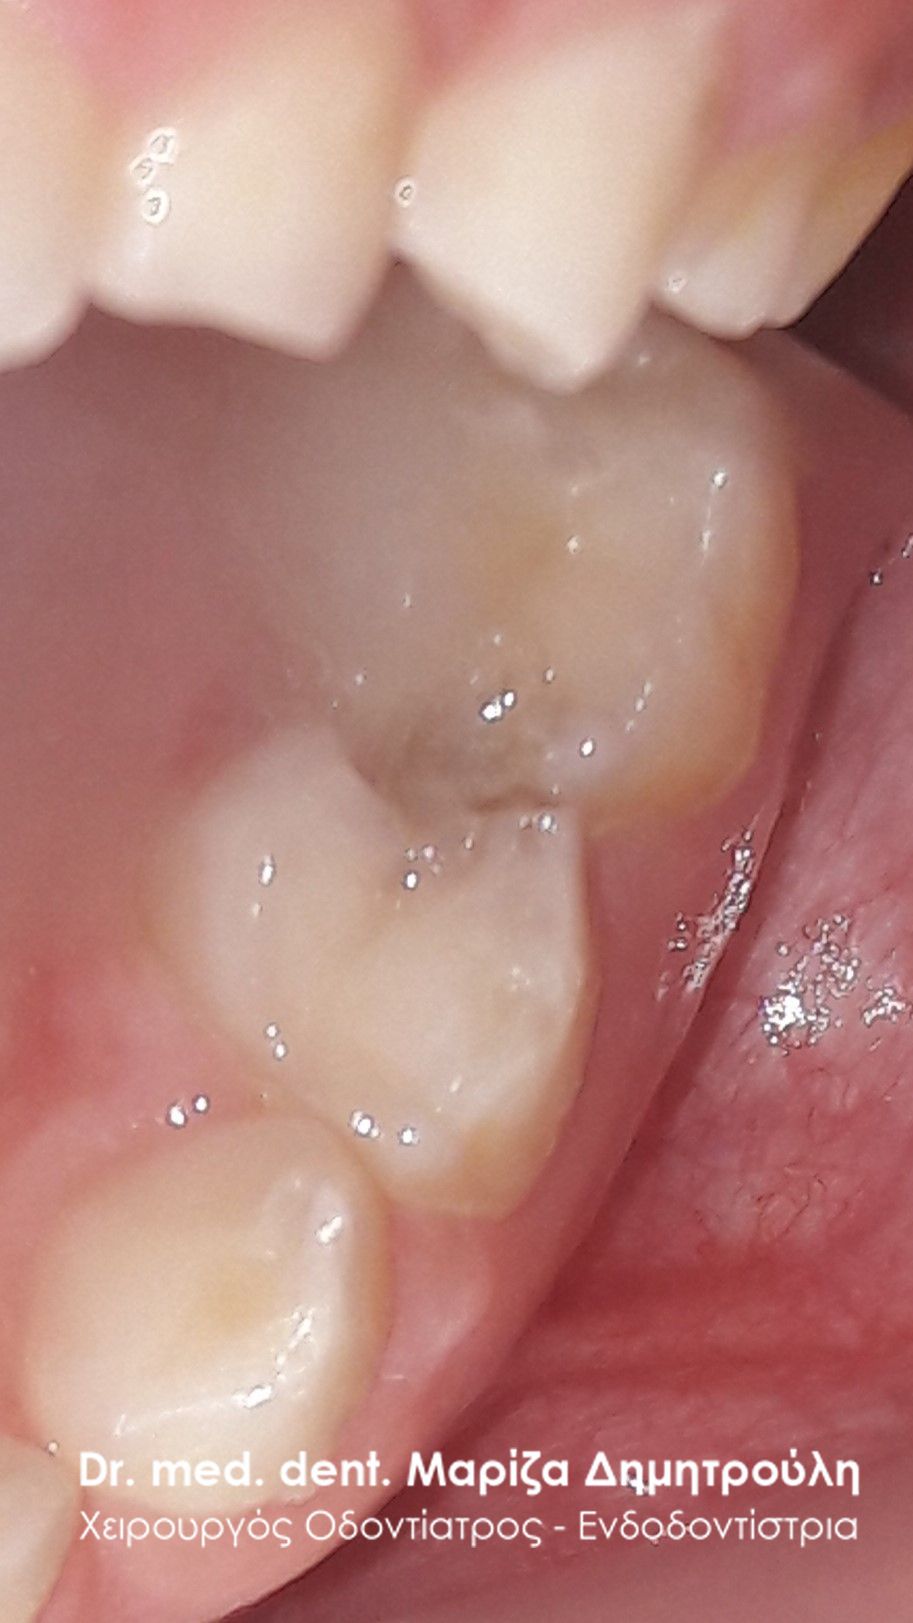

ΠΡΙΝ

ΜΕΤΑ – Σφράγισμα νεογιλού δοντιού και sealant μόνιμου δοντιού